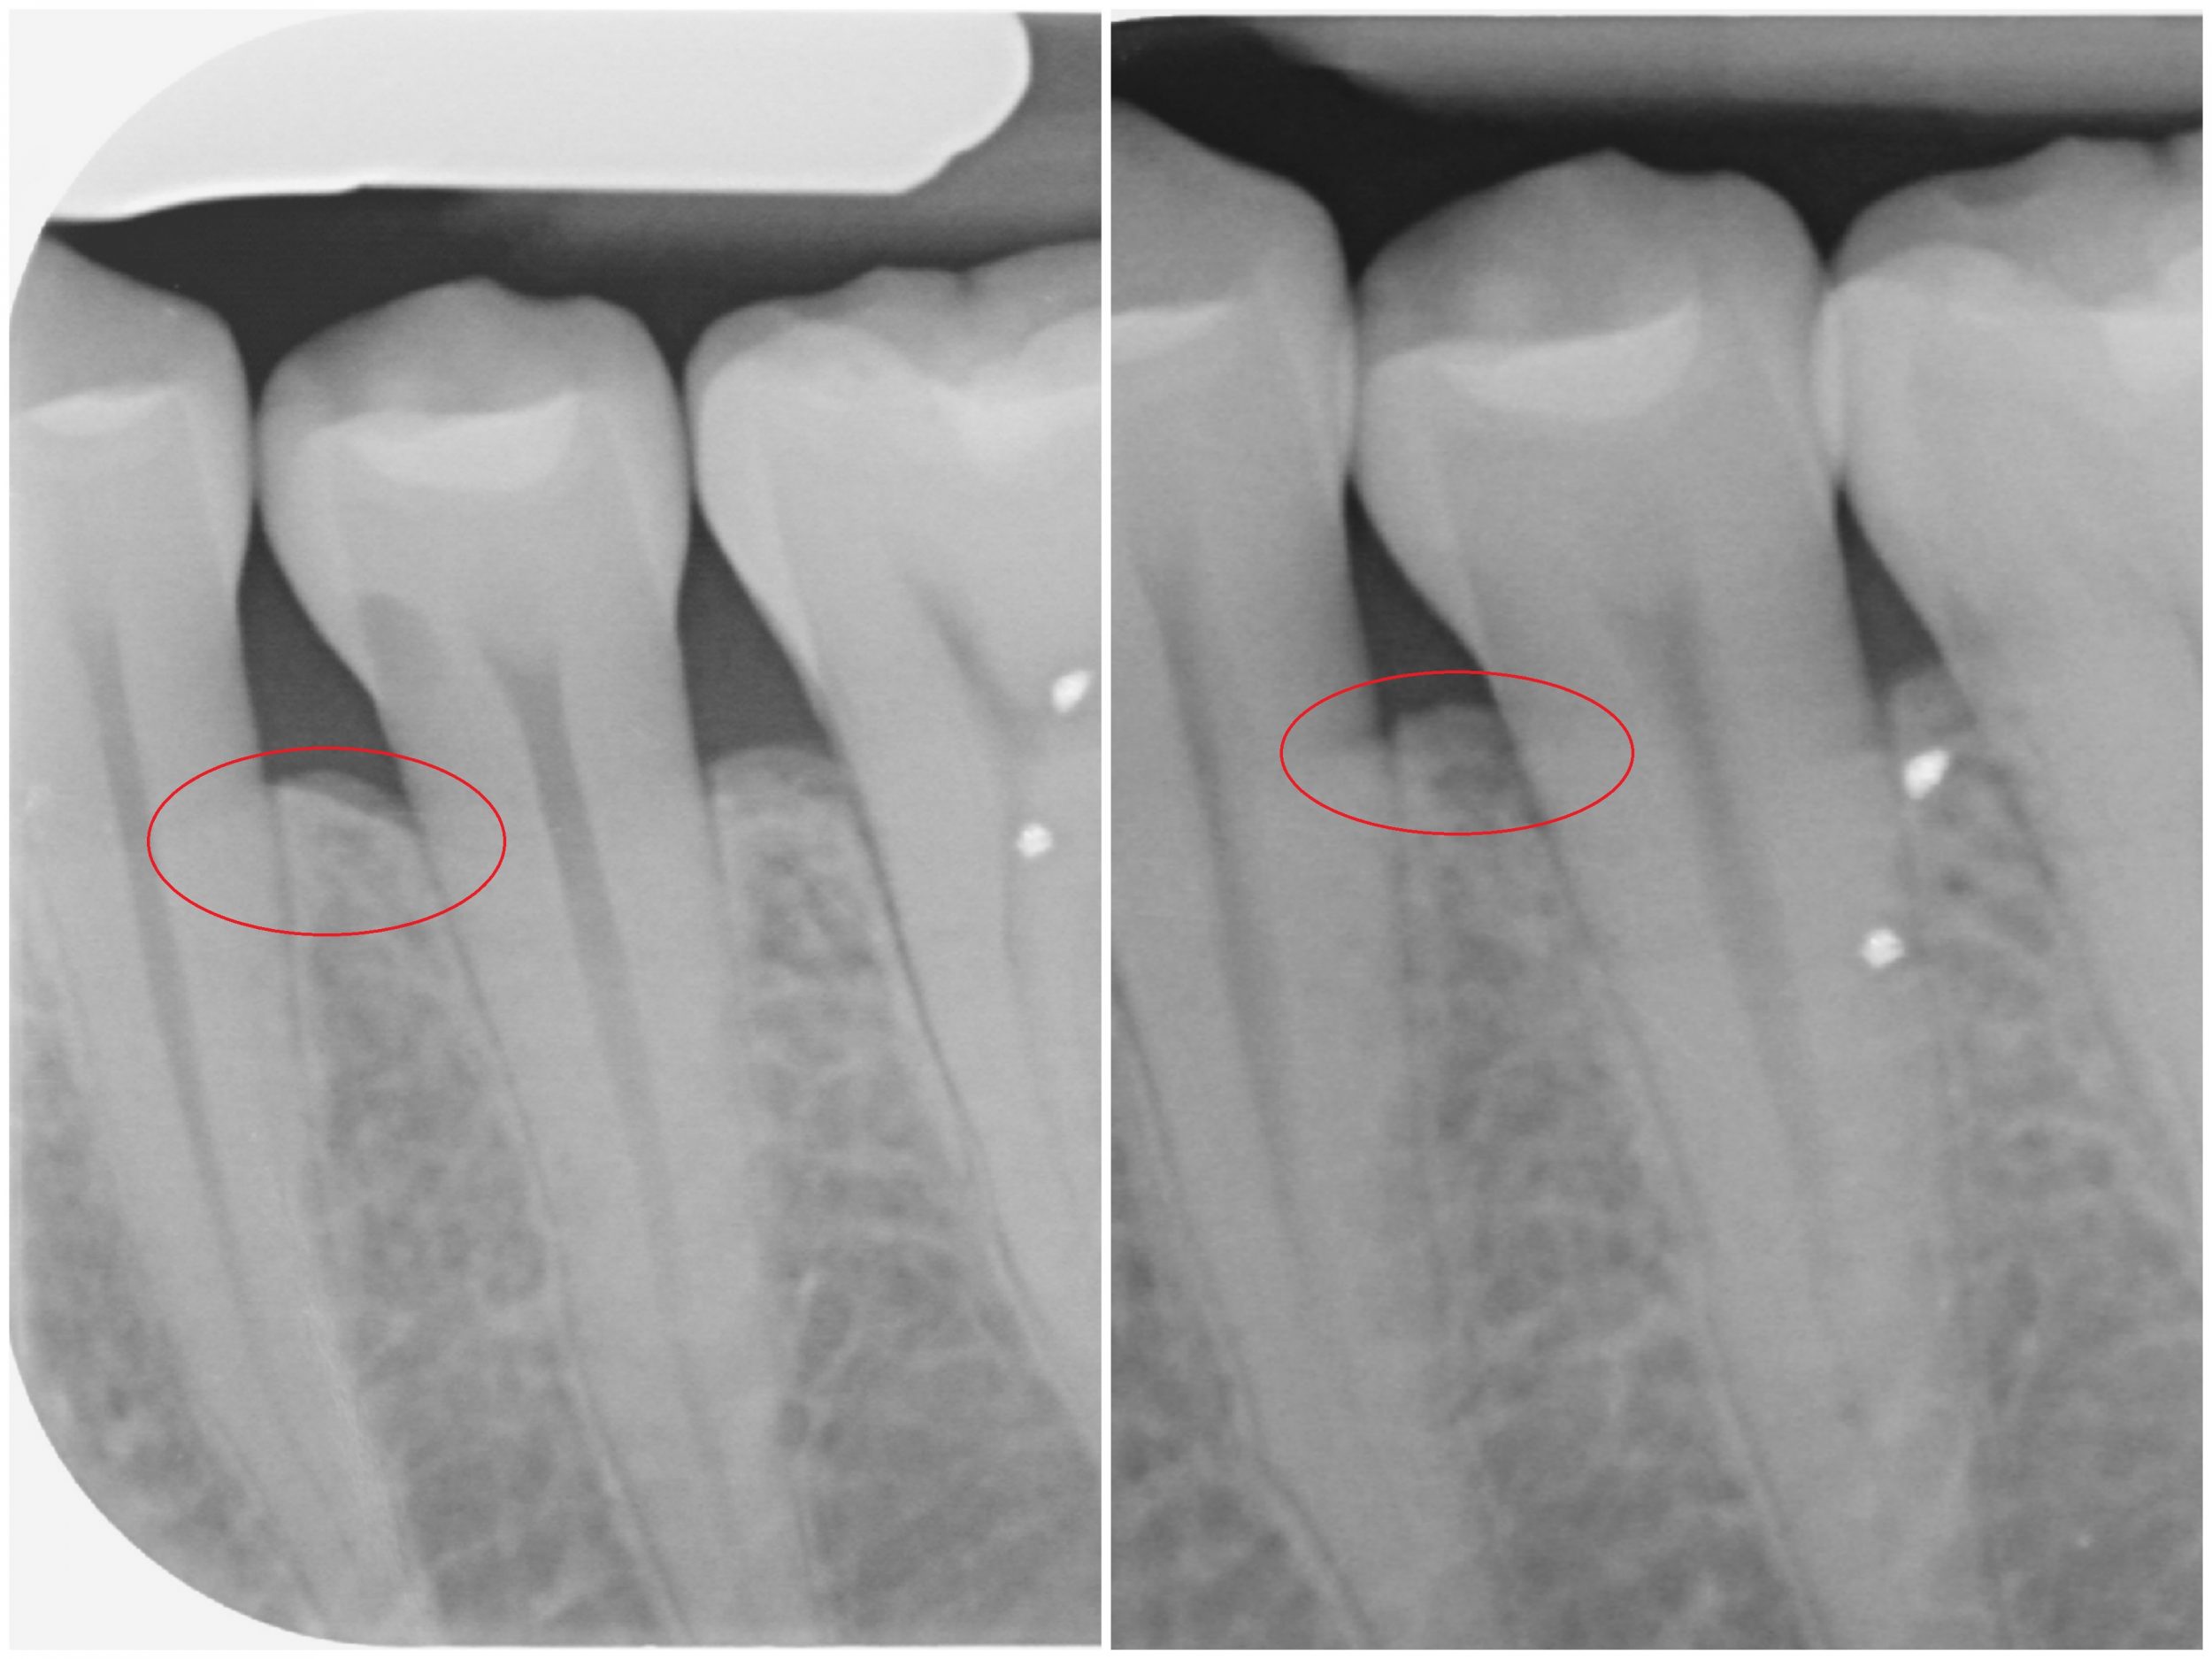

Ora che le mie gengive e i miei denti sono ultra puliti, posso tornare per una detartrasi ogni 6 mesi. Allo stesso tempo, stavo bevendo l’acqua Quinton e sembra rigenerare il mio osso, non so come spiegarlo, ma ecco le radiografie prima/dopo:

Buone notizie ricevute questa mattina: questi trattamenti sono stati rimborsati al -50% dalla mia assicurazione di viaggio. La sicurezza sociale francese richiede documenti supplementari (in linea di principio, le cure fornite in altri paesi dell’Unione europea possono essere coperte fino al livello della scala francese, ma è a discrezione della sicurezza sociale). Per continuare…